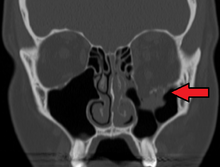

Radiography, imaging of tissues using X-rays, is used to rule out facial fractures.[2] Angiography (X-rays taken of the inside of blood vessels) can be used to locate the source of bleeding.[10] However the complex bones and tissues of the face can make it difficult to interpret plain radiographs; CT scanning is better for detecting fractures and examining soft tissues, and is often needed to determine whether surgery is necessary, but it is more expensive and difficult to obtain.[4] CT scanning is usually considered to be more definitive and better at detecting facial injuries than X-ray.[3] CT scanning is especially likely to be used in people with multiple injuries who need CT scans to assess for other injuries anyway.[11]

At the beginning of the 20th century, René Le Fort mapped typical locations for facial fractures; these are now known as Le Fort I, II, and III fractures (right).[6] Le Fort I fractures, also called Guérin or horizontal maxillary fractures,[13] involve the maxilla, separating it from the palate.[14] Le Fort II fractures, also called pyramidal fractures of the maxilla,[15] cross the nasal bones and the orbital rim.[14] Le Fort III fractures, also called craniofacial disjunction and transverse facial fractures,[16] cross the front of the maxilla and involve the lacrimal bone, the lamina papyracea, and the orbital floor, and often involve the ethmoid bone.[14] are the most serious.[17] Le Fort fractures, which account for 10–20% of facial fractures, are often associated with other serious injuries.[14] Le Fort made his classifications based on work with cadaver skulls, and the classification system has been criticized as imprecise and simplistic since most midface fractures involve a combination of Le Fort fractures.[14] Although most facial fractures do not follow the patterns described by Le Fort precisely, the system is still used to categorize injuries.[5]